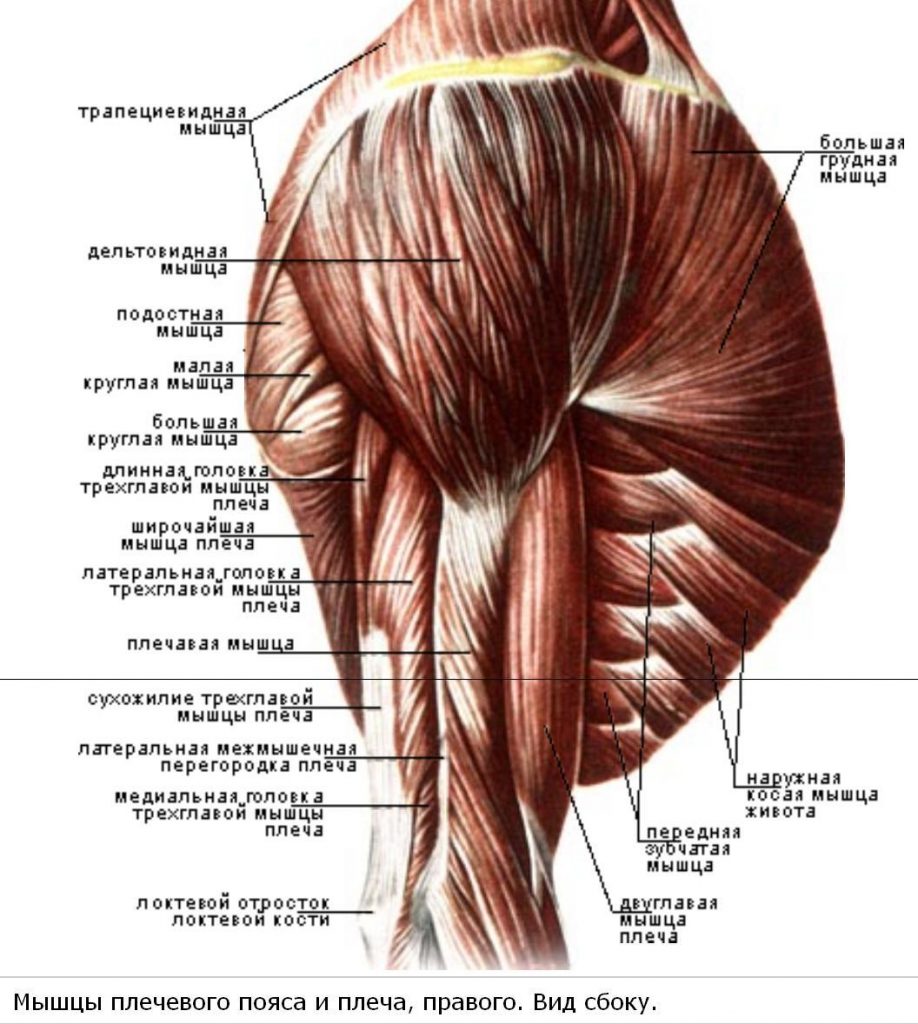

Фотографии поддельтовидной мышцы плечевого сустава

Раздел: Образы вокруг